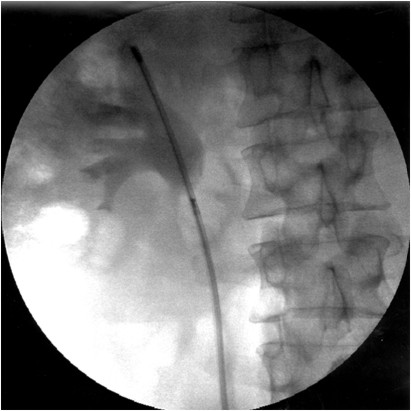

Интраоперационная рентгенография: фиброуретеропиелоскоп в полостной системе почки